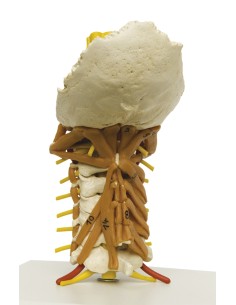

Dal cranio in 22 parti con incastri magnetici ai modelli di colonna vertebrale, da quelli di articolazioni a quelli di cuore, ogni pezzo della nostra collezione è progettato per un’immersione totale nello studio dell’anatomia umana. I nostri modelli, realizzati tramite scansioni di ossa vere, garantiscono un’esperienza tattile autentica e una fedeltà di peso quasi identica agli originali.

Essenziali per studenti e professionisti, i nostri modelli anatomici sono strumenti didattici che permettono di osservare le strutture anatomiche con precisione, eliminando la necessità di dissezioni o studi invasivi. Sono inoltre utili per spiegare ai pazienti le patologie, rendendo la comunicazione più efficace e risparmiando tempo prezioso.